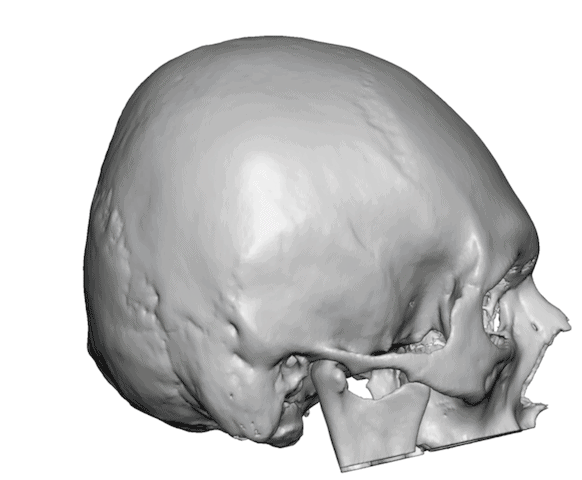

Desire for rounder shape to the top of the head from a congenital parasagittal deficiency skull shape.

Custom skull implant designed to fill in the parasagittal deficiencies.

Desire for rounder shape to the top of the head from a congenital parasagittal deficiency skull shape.

Custom skull implant designed to fill in the parasagittal deficiencies.